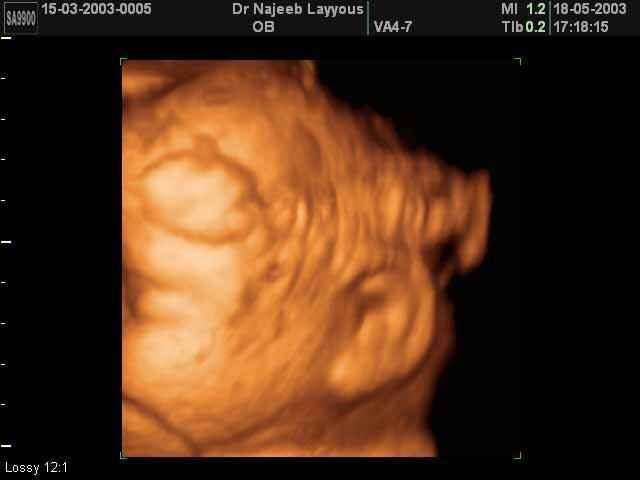

- Fetal Parts Ultrasound Scan Photos